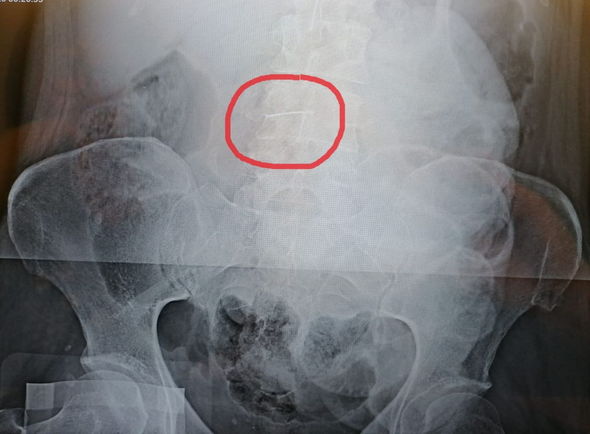

Həkimlərin sözlərinə görə, zərərçəkən mədə-bağırsaq qanaxması şübhəsi ilə təcili yardım maşını ilə xəstəxanaya aparılıb. Diaqnoz təsdiqlənməyib, lakin qarın boşluğunun rentgenoqrafiyası zamanı həkimlər xəstənin bədənində yad cisim görüblər. Bunun tikiş iynəsi olduğunu anlayanda isə qadının xilası üçün təcili əməliyyat qərarı verilib.

Həkimlər yad cismi hər an qarın boşluğunda hərəkət etməyə başlayacaq və düzəlməz nəticələrə gətirib çıxara biləcək “saatlı bomba” adlandırıblar.

“Əməliyyat uğurlu keçdi, cərrahlar rentgen nəzarəti altında beş sm uzunluğunda iynəni çıxardılar, xəstə hazırda sağalır”, – Səhiyyə İdarəsindən xəbər verilib.